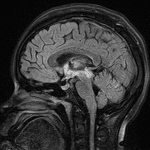

Age: 17

Sex: Female

Indication: Encephalopathy

Case #27

- T2/FLAIR signal hyperintensity in the right greater than left thalami and right greater than left dorsal midbrain with involvement of the periaqueductal gray matter, hypothalamus, anterior commissure, and mamillary bodies

- Areas of cystic change in the right thalamus and right eccentric midbrain

- No corresponding enhancement or restricted diffusion

- No substantial intracranial mass effect or evidence of hydrocephalus

Neuromyelitis optica (NMO)